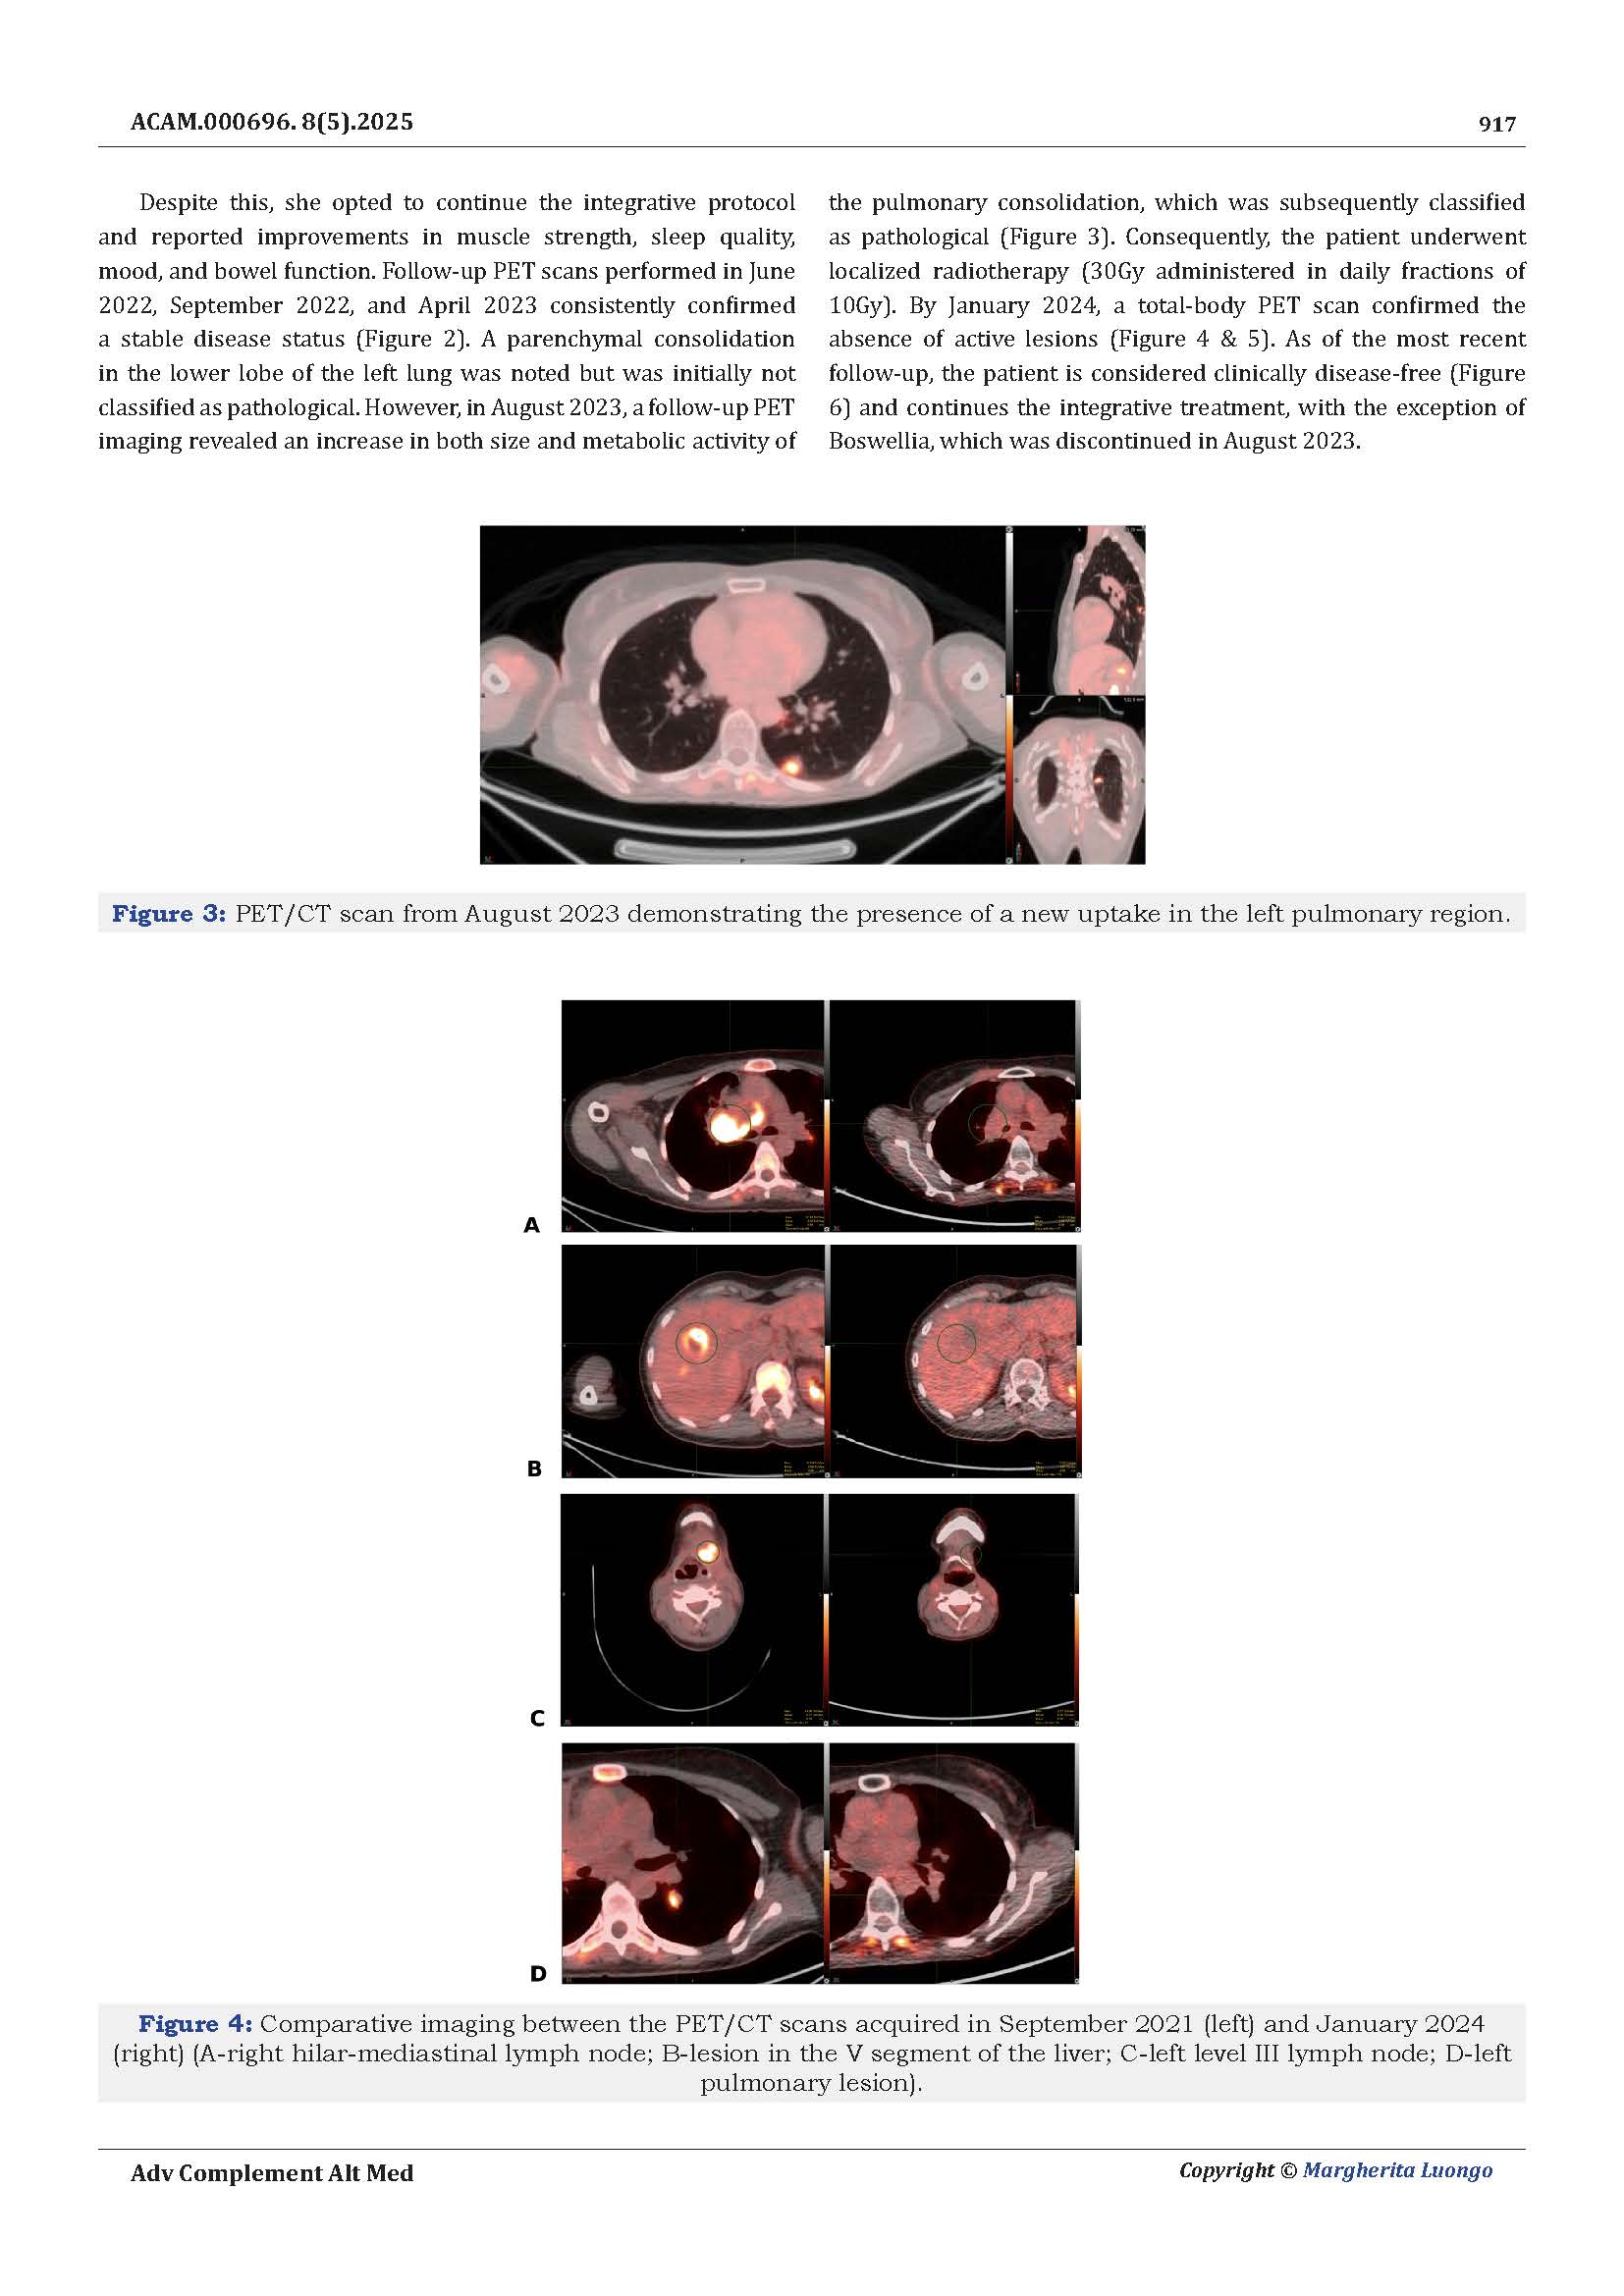

Dopo sei anni di monitoraggi costanti, le risonanze magnetiche hanno mostrato la stabilità della massa tumorale, senza progressione della malattia.